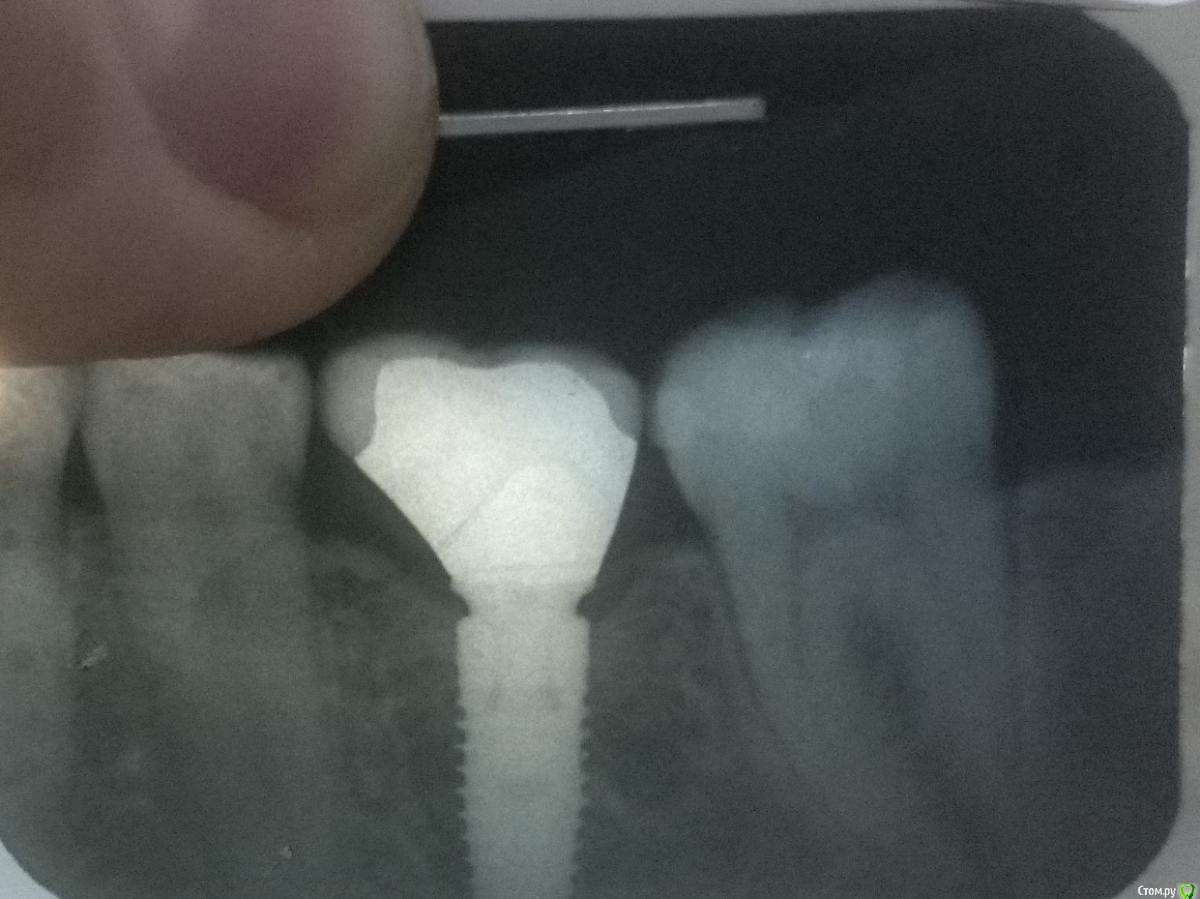

kramer Опубликовано 28 августа, 2019 Поделиться Опубликовано 28 августа, 2019 Всем здравствуйте. История такая: отсроченная имплантация, торк 40, формирователь. Платформа получилась довольно язычно, так что вестибулярно тканей было с некоторым избытком. Через 3 месяца после имплантации зову на оттиски, замечаю что формирователь подвижен (жалоб не было). Снимаю его, убираю наросшую десну из шахты, отправляю на 2 недели отдыхать. Через 2 недели изготавливается временная коронка. Фиксирую, через 2 недели первый эпизод свища. Коронка подвижна. Откручиваю (ослабления винта не было), все промываю. Переделываю временную коронку, фиксирую, все норм. Через несколько недель делаю постоянную коронку из диоксида циркония. Спустя 3 месяца опять свищ, вестибулярно на том же месте. Коронка стоит неподвижно. Зондирование патологических карманов не выявило. Дефицита кератинизированной десны нет. Гигиена норм. В чем может быть причина? КТ скоро будет. Ссылка на комментарий

bullbull Опубликовано 29 августа, 2019 Поделиться Опубликовано 29 августа, 2019 Снимок с гутаперчей в свище. Пройтись ультразвуком, промыть и метрогил туда закачать. Ссылка на комментарий

Irouil Опубликовано 30 августа, 2019 Поделиться Опубликовано 30 августа, 2019 (изменено) Это СС же, какой там тонкий участок? Да и на снимке резорбции нет совсем, винт не причём, имхо Изменено 30 августа, 2019 пользователем Irouil 1 Ссылка на комментарий